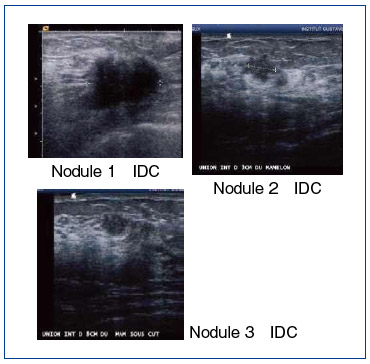

症例1は,53歳,女性。触診にて4cmの固い腫瘤が認められた。通常のマンモグラフィでは,dense breastのため病変は描出されなかった(図1 b,c)。超音波では,悪性を疑うような不整形の腫瘤が認められ,その周辺に2つの小さな病変が認められた(図2)。針生検の結果,3つの病変はいずれも浸潤性乳管癌と診断されたが,従来のマンモグラフィではdense breastの診断は困難であることが改めて確認された。

図2 症例1の超音波画像

(画像ご提供:フランス・IGRのご厚意による) |